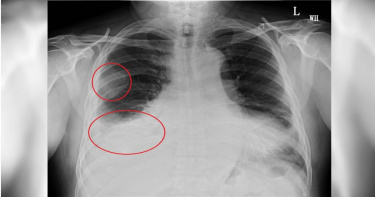

近日有位精神跟食慾很差的病患到醫院掛急診,驗出PCR陽性,但CT值29所以很快就轉出隔離病房,但醫師一看他的資料,又把他隔離起來,原來病患可能罹患肺結核。胸腔科醫師蘇一峰27日在臉書發文說,「一位精神差食慾差的病人,一到急診室驗出PCR陽性,但是CT值高(29)病毒不多,所以很快就轉出隔離病房了」,但他看了病患的資料,又把病人隔離起來,要網友猜看看是為什麼?此文曝光後,網友紛紛留言回應「肺結核」、「是TB嗎?」、「連我這個醫學的門外漢都看得出來,情況不妙了,而且蘇醫師把病人關起來一定是非常緊急而且迫切會傳染的病因」、「结核病Tuberculosis,又叫TB」、「看皮下脂肪,預後應該很爛」。而蘇一峰也在文章的留言區中公布答案,「大家答對了,就是肺結核,痰裡面有滿滿的結核菌,X光是肺結核的典型表現,所以高度懷疑肺結核」,而病患目前在加護病房治療中,希望能救到他。據衛福部資料指出,結核病是一種慢性傳染病,男性發生比率較高,老人比發病率比年輕人高,結核病主要透過飛沫與空氣傳染,一旦發病症狀為咳嗽超過2週、體重減輕、發燒等。目前已有有效抗結核藥物治療,只要依照醫師提供的治療處方規則治療,結核病是可以治癒的。